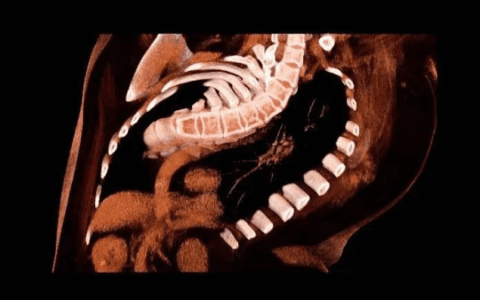

考虑到王先生的情况有可能进一部感染扩散至颅内及纵隔,若病情快速恶化,易诱发脓毒血症,甚至造成多器官功能衰竭等严重并发症,危及生命。因此,介入超声科团队紧急组织院内多学科及科室内部讨论后,认为目前除了抗感染治疗、全身综合治疗以外,应重点考虑如何让脓肿得到充分引流,但颜面部及头颈部为人体暴露部位,且组织间隙脓肿比较散、面积大,使用外科手术创伤大、风险大,尤其对糖尿病患者而言伤口难愈合,因此几乎不考虑外科手术。紧急时刻,郭建琴主任带领团队,反复超声查看病人病灶后,讨论决定实施脓肿穿刺置管引流术。术中,结合CT定位,郭建琴主任团队在超声引导下应用多种穿刺技巧,避开风险部位及血管成功地进行了多管、粗管的充分引流。在介入超声科医生每日的反复冲洗、充分引流下王先生病情得到好转,成功救治28天后王先生完全康复出院,为此他和家属感动不已。